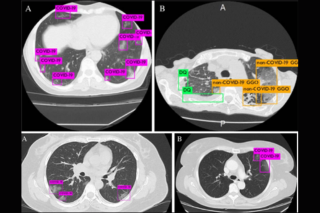

Methods: 904 axial lung window CT slices from 338 patients in 17 countries were collected and labeled. The data included 606 images from COVID-19 positive patients (confirmed via RT-PCR), 224 images of a variety of other pulmonary diseases including viral pneumonias, and 74 images of normal patients. We developed, trained, validated, and tested an object detection model which detects features in three categories: ground-glass opacities (GGOs) for COVID-19, GGOs for non-COVID-19 diseases, and features that are inconsistent with a COVID-19 diagnosis. These collected features are passed into an interpretable decision tree model to make a suggested diagnosis.